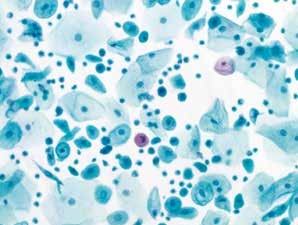

图7-5 满意样本(中倍、液基、巴氏染色)

正常子宫颈管腺细胞,蜂窝状排列,足够数量的鳞状上皮细胞,炎细胞背景。